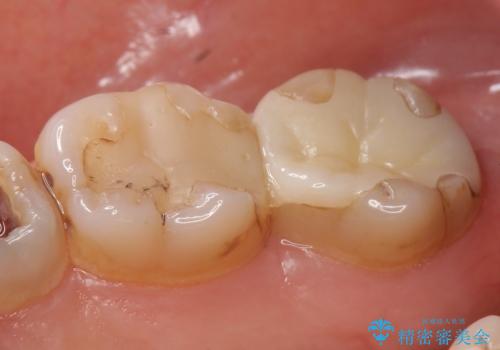

- 昔治療した奥歯の見た目が気になるのでセラミックでやり直したいといらっしゃった方の症例です。

右下6、7の古い詰め物および虫歯を除去後、オールセラミッククラウンによる補綴を行いました。